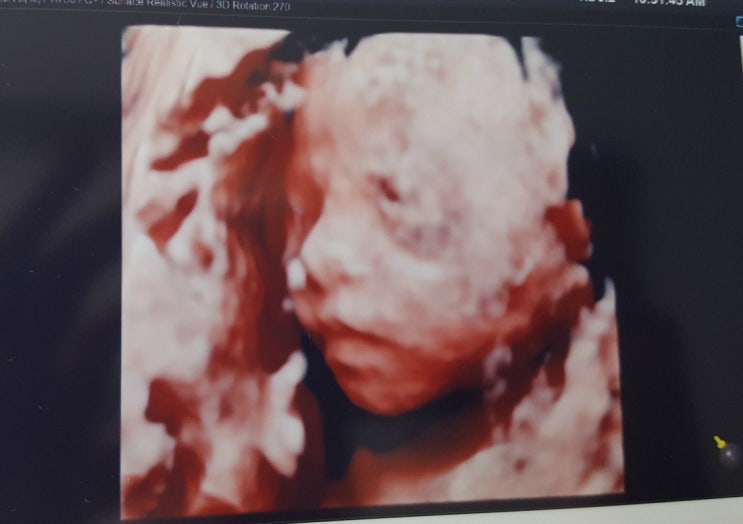

[둘째 임신주수별 진료] 임당검사, 정밀초음파 ☆ 임신24주4일 ☆ 2017.07.13

둘째 임신주수별 진료 임당검사, 정밀초음파 임신 24주 4일 2017.07.13 진료비: 28,000원 쑥쑥이 얼굴~~^^ ...